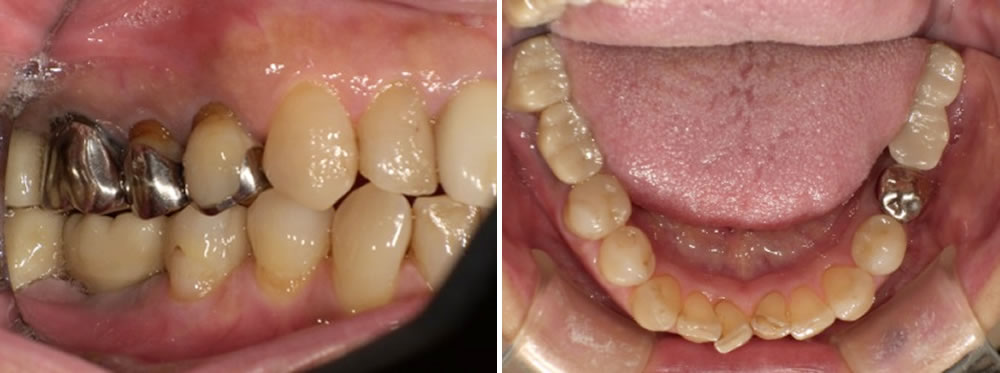

3週間後、被せ物が出来上がり、適合と見た目を確認した後に装着しました。装着後に咬み合わせの確認・調整を行って治療完了となりました。ブリッジよりも清掃性が良くなり見た目も良くなりました。